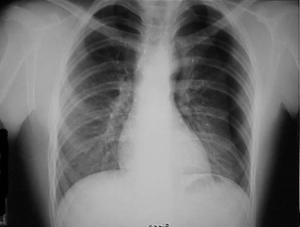

Pneumotorace simplu stang Pneumotorace

simplu stang

Pneumotorace